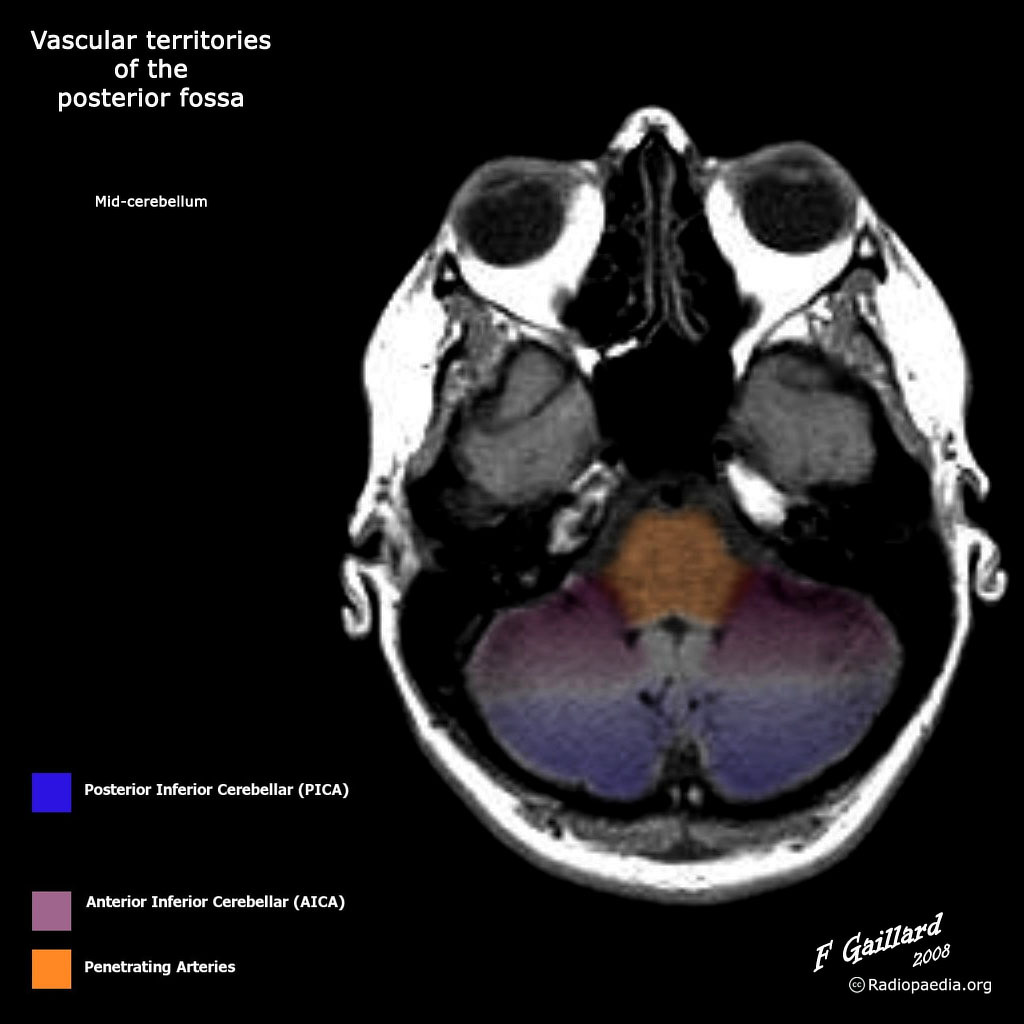

Posterior fossa vascular territories (illustration) Image Radiopaedia Vascular Territories Gaillard f, vascular territories of the lateral cerebral cortex (illustration). There is significant variation in many textbooks and other resources describing the venous vascular territories of the brain. Typical appearances of hemorrhagic transformation following a large mca territory stroke. The brain/cerebrum is supplied by the anterior, middle and posterior cerebral arteries. Case study, radiopaedia.org (accessed on 31 may 2024). Learn. Radiopaedia Vascular Territories.